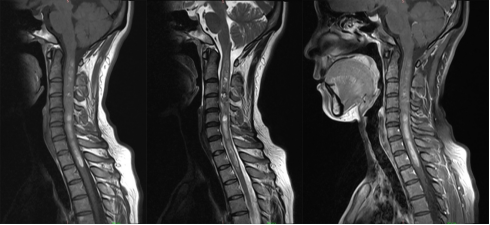

图5.颈段髓内海绵状血管瘤伴出血MRI图像